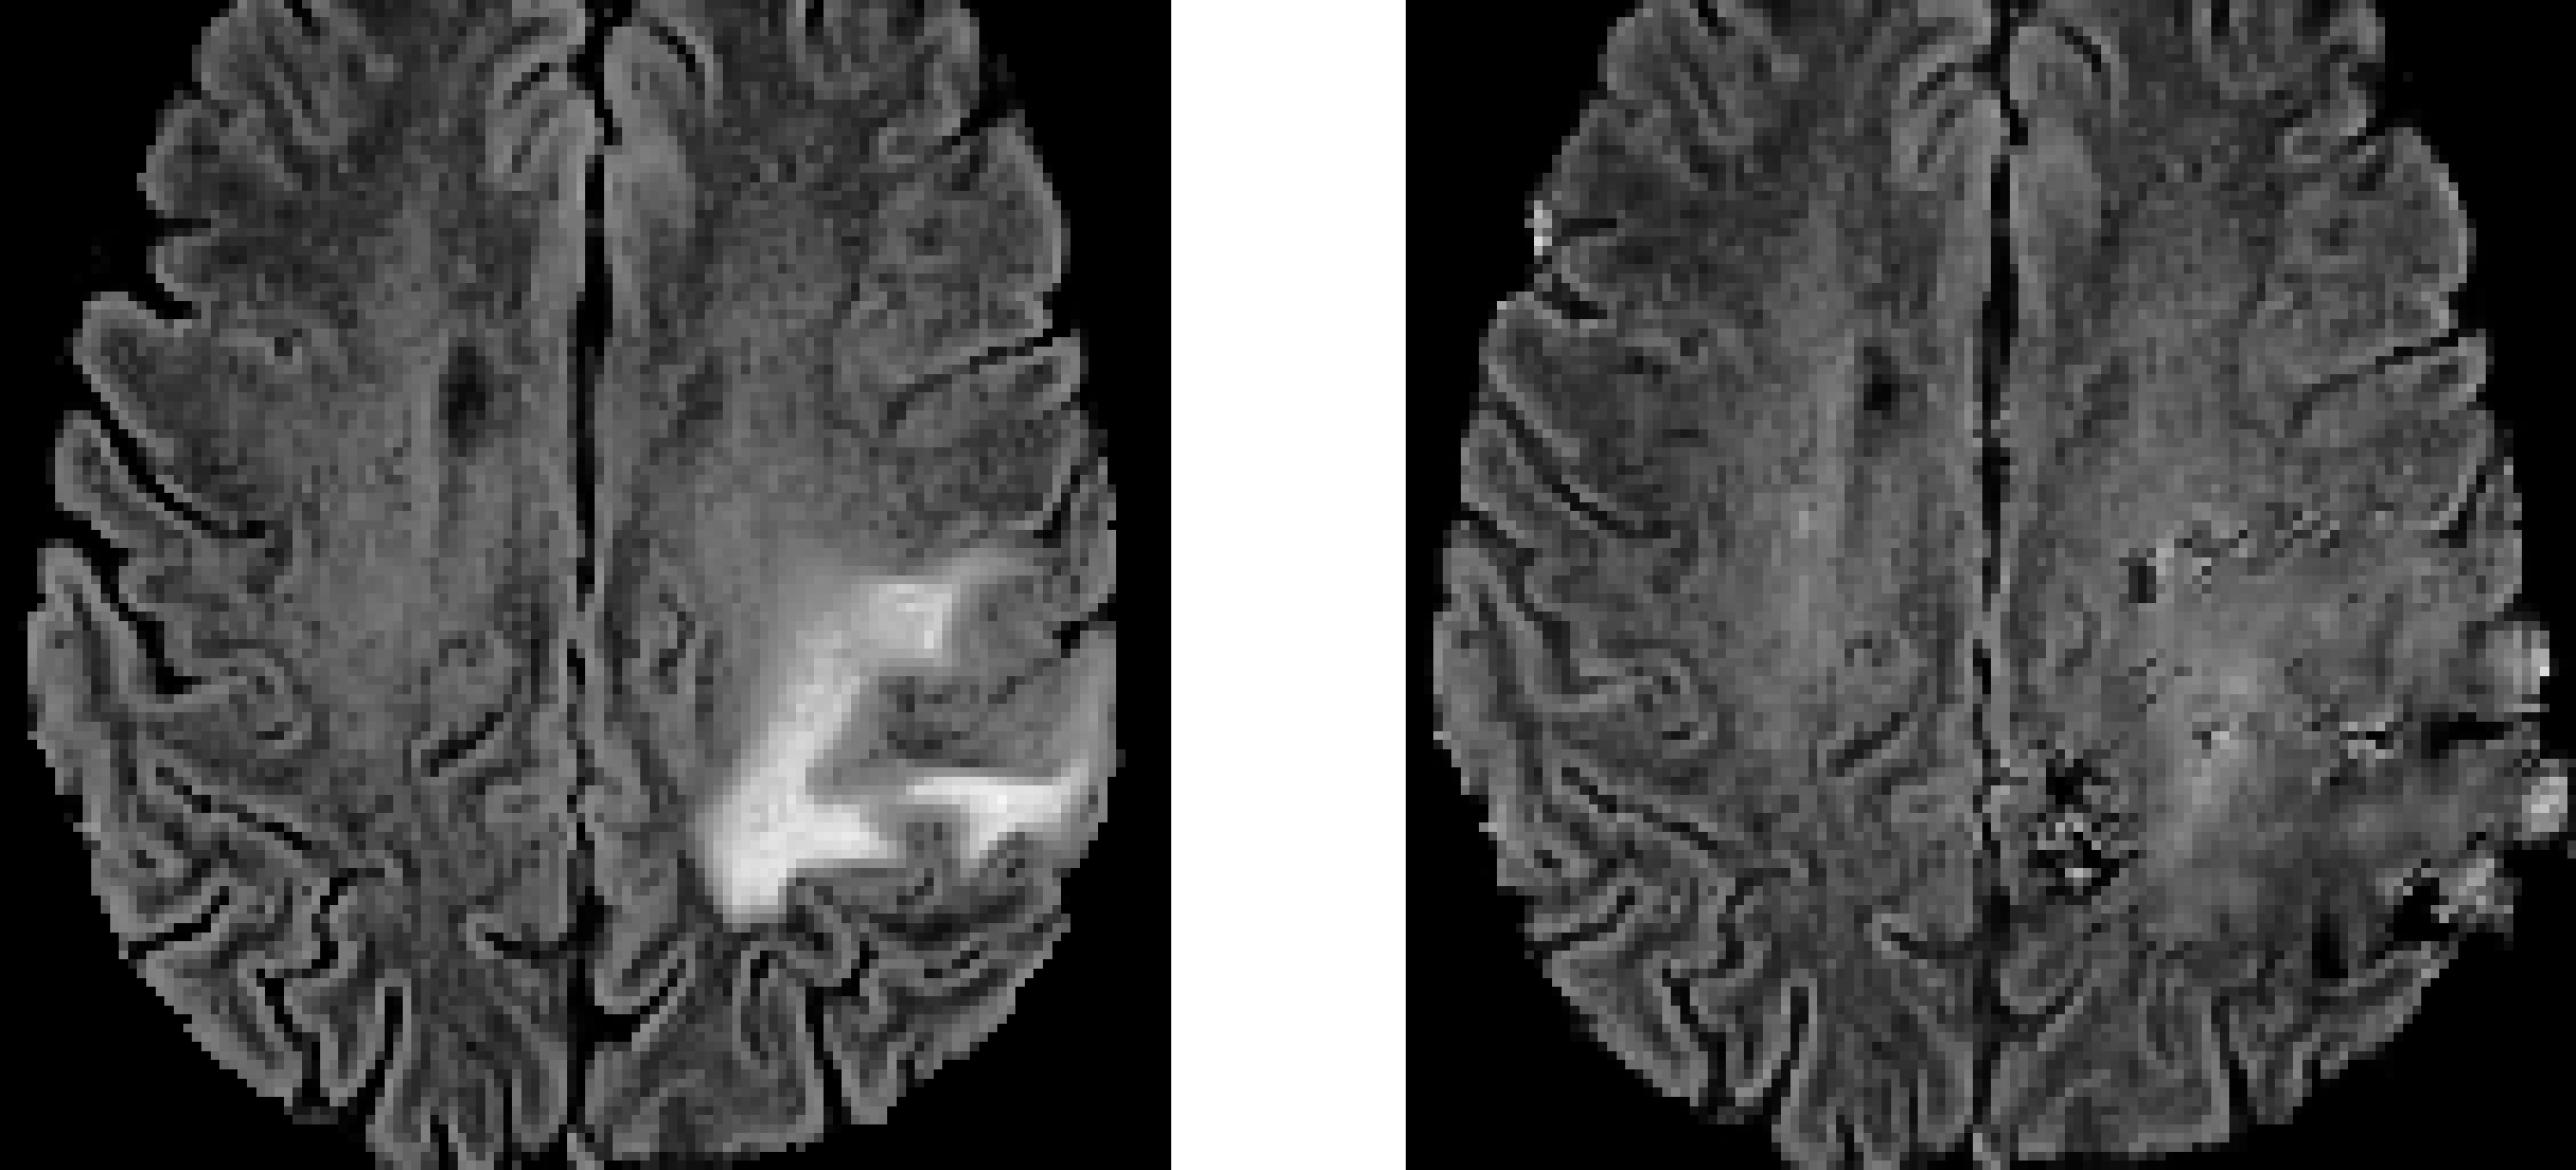

Examples of cancerous MR images and their generated non-cancerous variants are presented in Figure 5. Examples of cancerous MR images, their generated segmentations, and their true segmentations are visualized in Figure 6.

Refer to caption

(a) Example 1.

(b) Example 2.

Fig. 5: Examples of MR image FLAIR channel (left) and their generated non-cancerous variant (right).